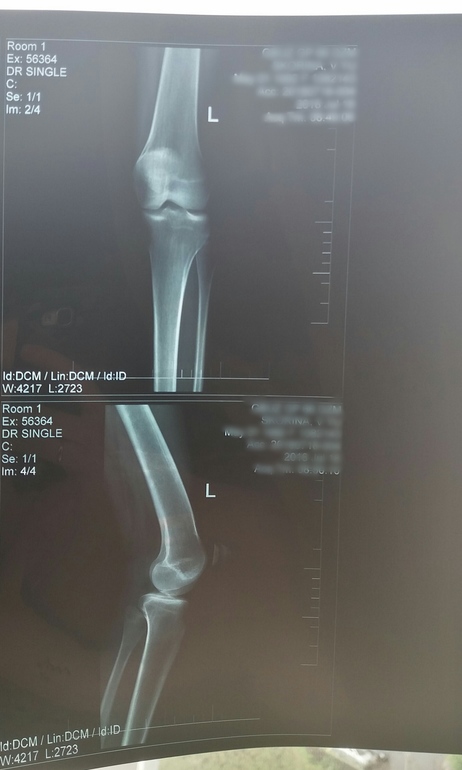

Гонартроз и остеофиты

Опорно-двигательный аппаратСделала снимок, к ортопеду 2 августа только. У кого-нибудь есть похожие проблемы? Как лечились, лекарства или операцией? Вдруг кто-нибудь понимает, насколько у меня всё плохо, снимок под кат

Я в снимках не разбираюсь, но у меня гонартроз коленных суставов 3 степени. Об операции пока не говорят, но очень настаивают на внутрисуставных уколах гиалуроновой кислоты. Я пока не соглашаюсь потому что во-первых не всем помогает, а во-вторых организм все таки должен сам восстанавливаться. А если колоть начать, то другое уже и не поможет. Огромные деньги стоит.